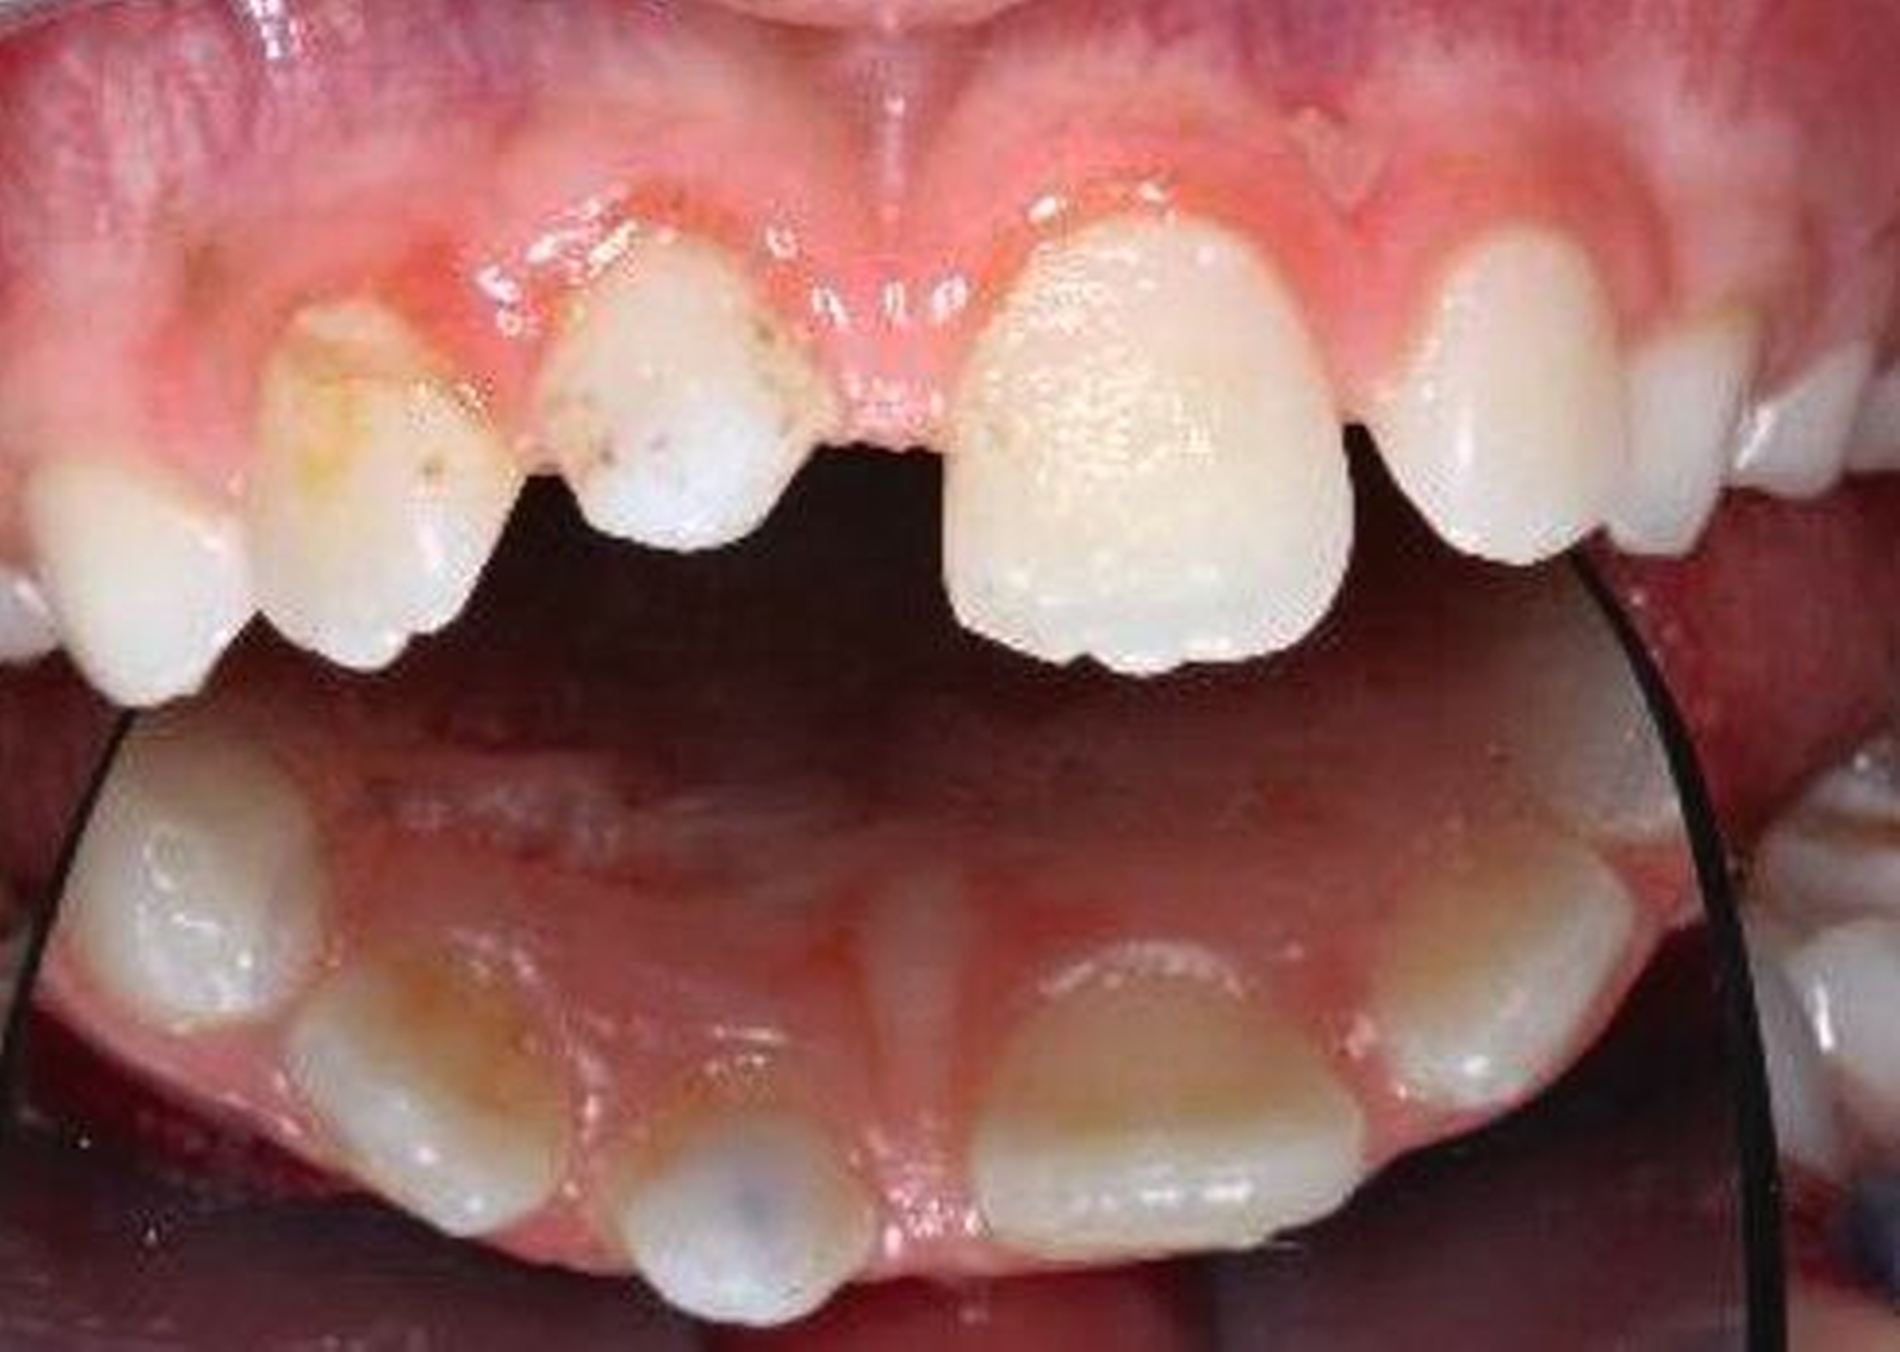

Nach der Einschätzung der Zellvitalität auf der oben genannten Basis folgt die therapeutische Intervention im Sinne der Replantation des betroffenen Zahnes in die gespülte Alveole (vorsichtige Entfernung des Blutkoagulums) mit steriler physiologischer Natriumchloridlösung. Schließlich muss die Replantation schonend erfolgen, da immer mit daran gedacht werden muss, dass es im Rahmen des Traumas zusätzlich zu einer Schädigung des Alveolarknochens gekommen sein kann (Abbildung 1). Diese Schädigung kann eine vollständige oder teilweise Alveolarfortsatzfraktur sein, die entsprechende Beachtung finden sollte. Im Anschluss erfolgt die Schienung des betroffenen Zahnes an den Nachbarzähnen. Dabei sollte ein Zeitraum von ein bis drei Wochen eingeplant werden (Tabelle 1).

Die Replantation sollte langsam und mit wenig Druck erfolgen, um eine zusätzliche Schädigung des Wurzelzements zu vermeiden. Anschließend sollte eine flexible Schienung des Zahnes erfolgen (Empfehlung 50) [Kahler et al., 2016].